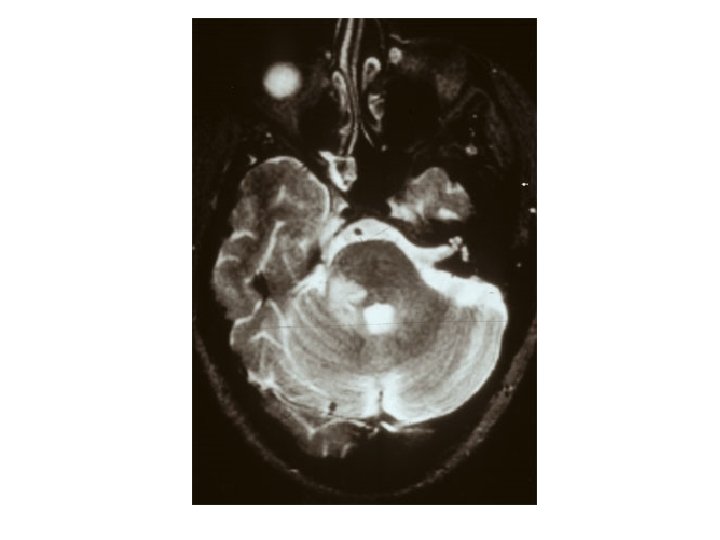

SEREBELLUMDA PLAKLAR